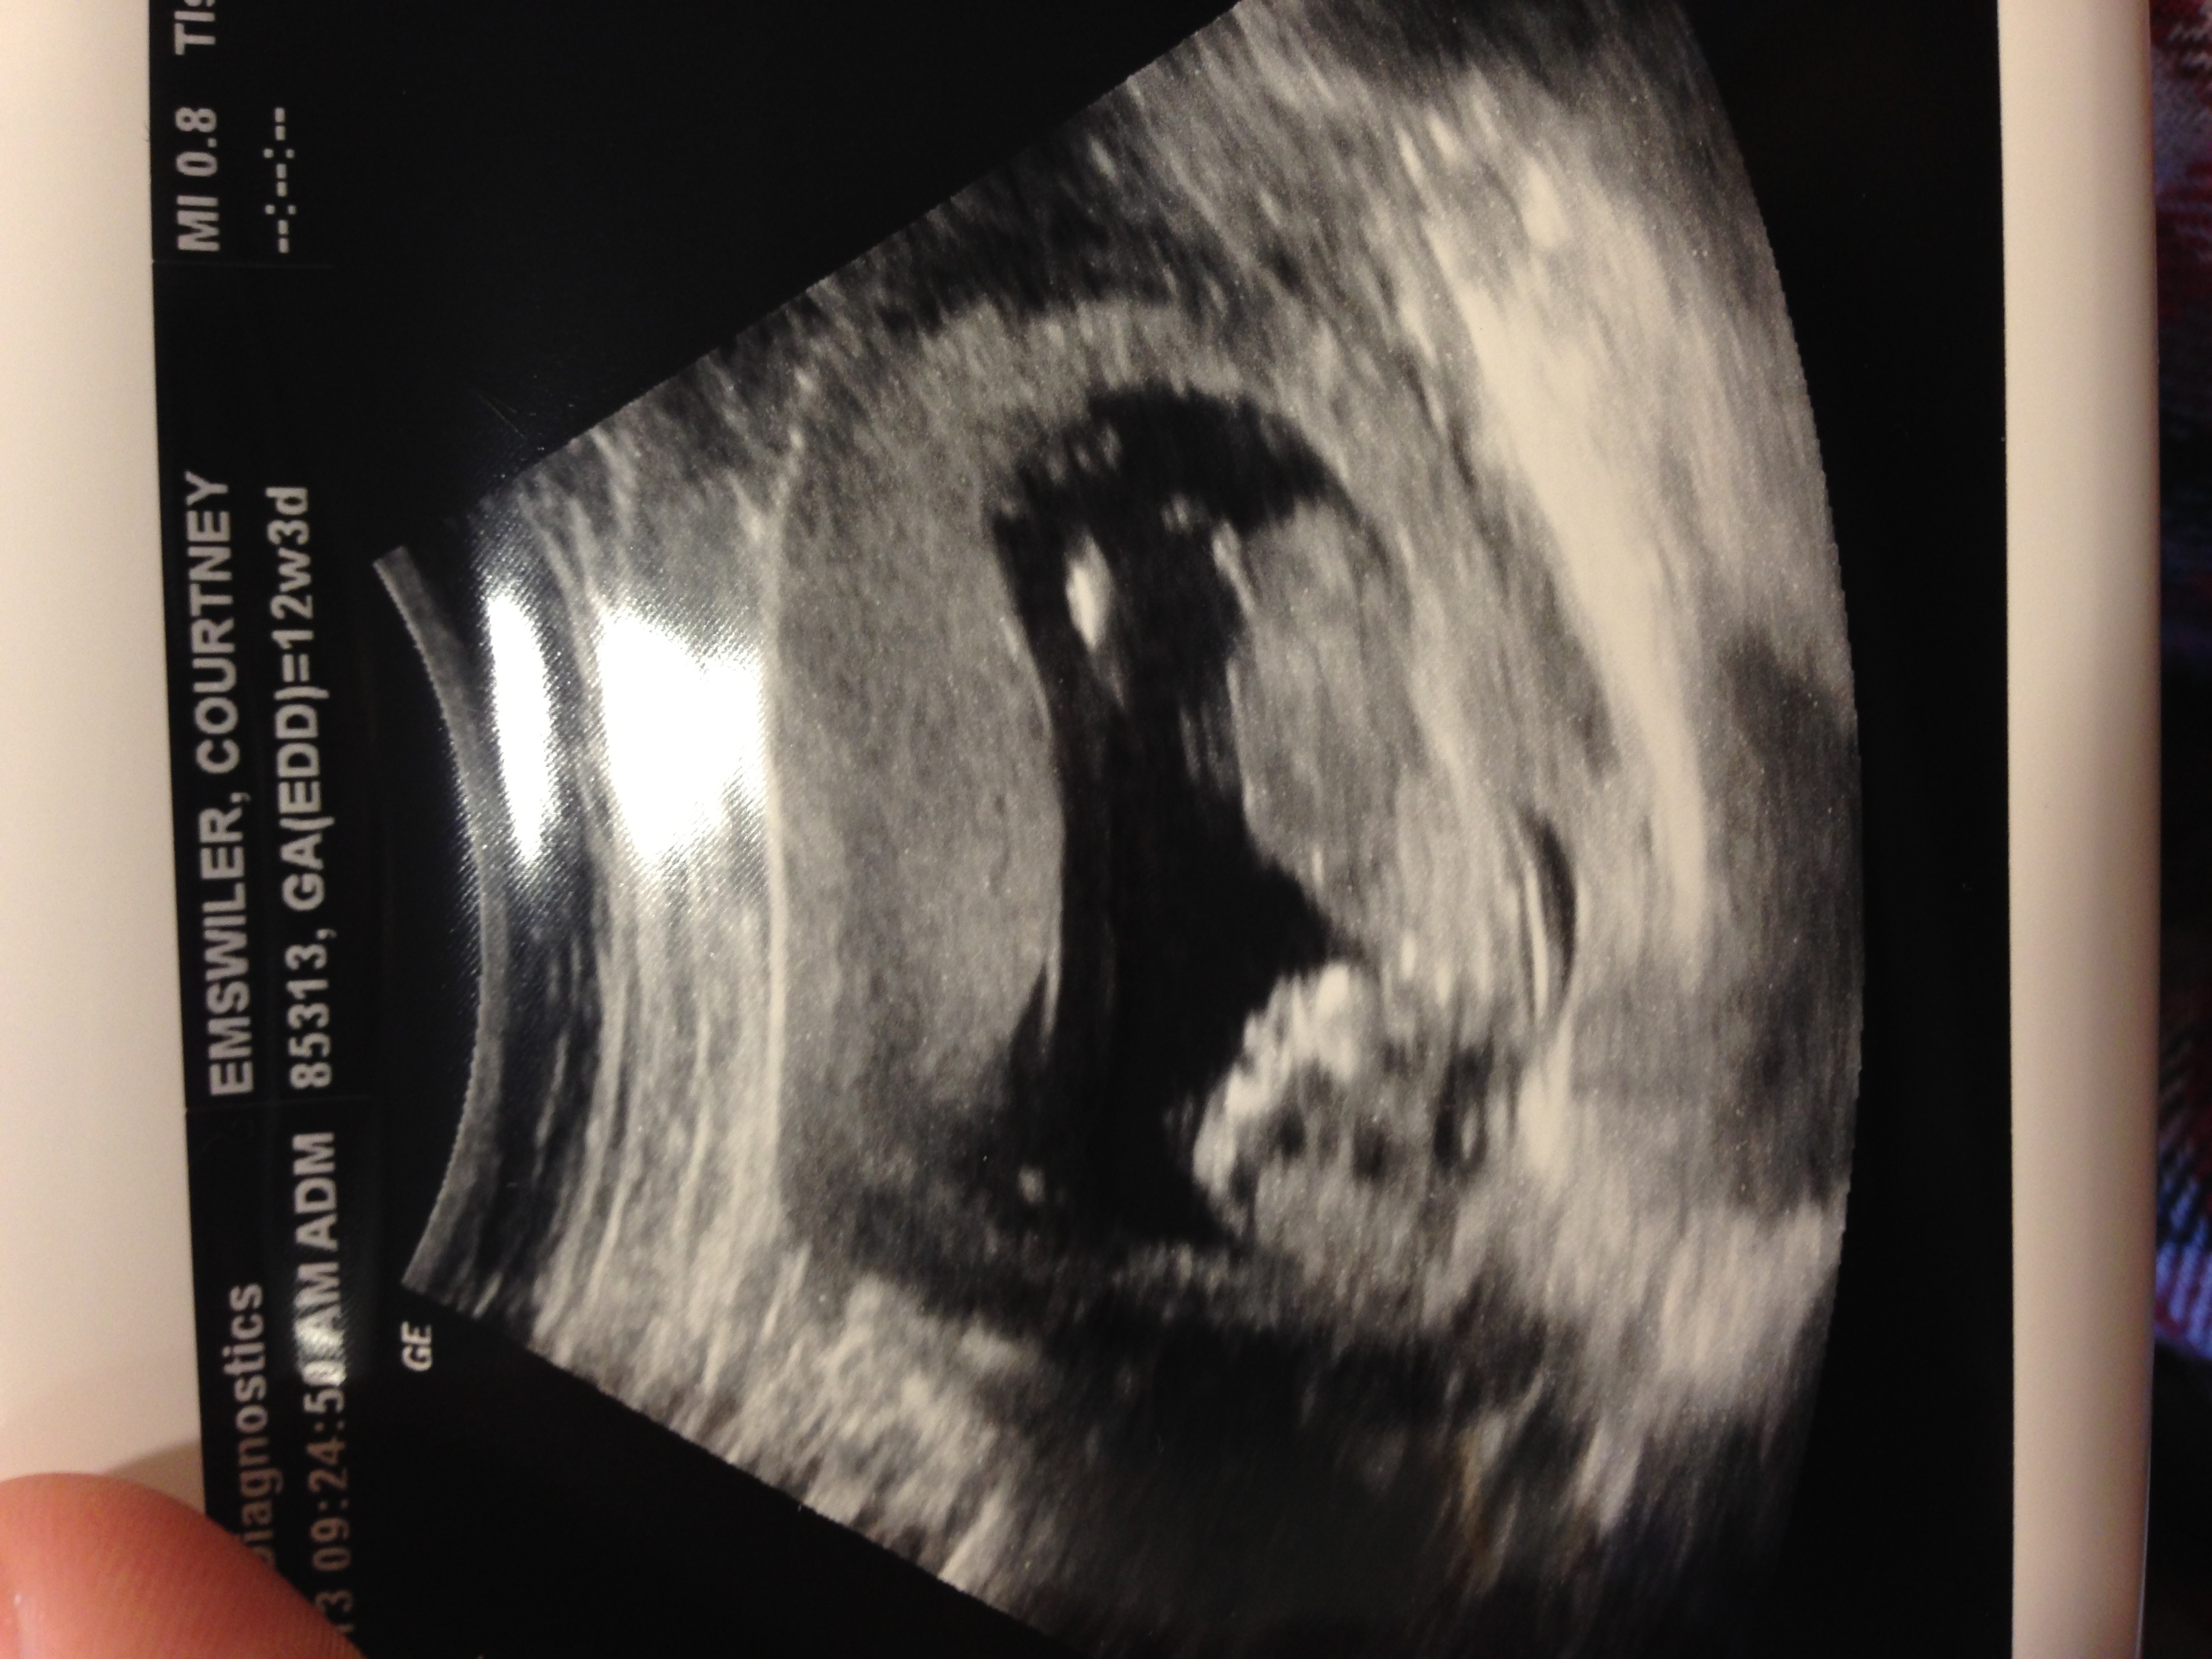

Looks girl to me

37 views and one reply... Does that mean you all agree with a girl?

looks like a girl!

Maybe girl

Hi i think it looks girly

looks girly x

50/50 for me maybe 2% more boy ??

I think girl, but find images like yours harder to be sure because LO is pushed down such that the spine is not completely visible.